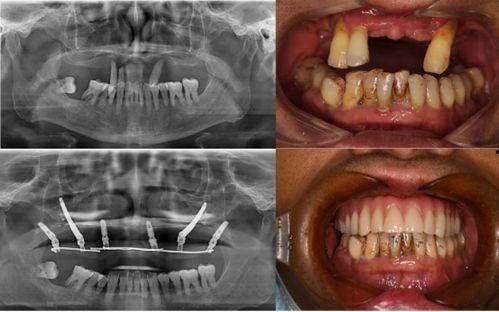

据患者们反映,他们在种植牙的过程中,遇到了种种问题。有的患者表示,医生在手术过程中操作不规范,导致种植牙失败;有的患者则抱怨,术后恢复期过长,而且效果并不理想。更有甚者,竟然出现了种植牙植入后,牙槽骨吸收的情况。

对于这起事件,口腔医学专家也给出了自己的看法。他们认为,种植牙是一项高风险的手术,需要医生具备丰富的经验和专业的技术。而这家口腔医院在种植牙过程中出现的问题,反映出我国口腔医疗行业在规范化、专业化方面还存在不少问题。